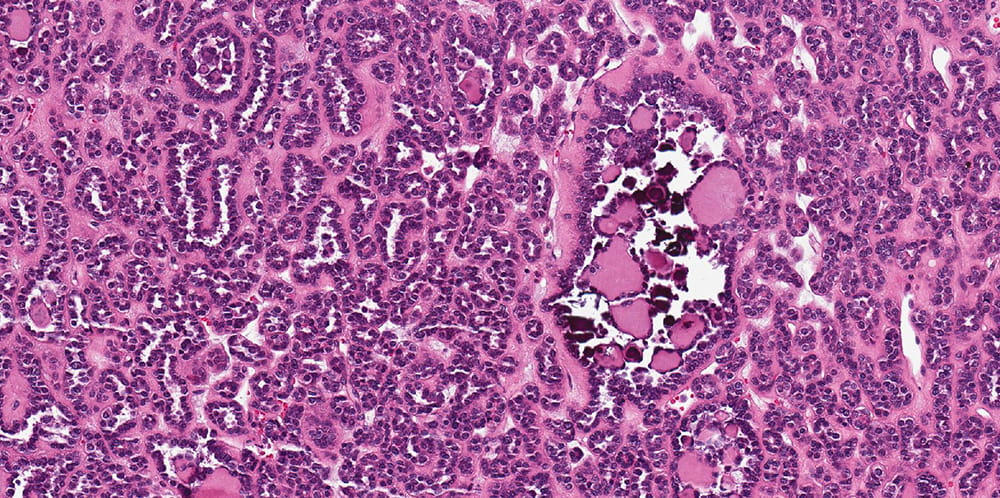

4.7 cm tan, well-circumscribed and focally hemorrhagic mass, confined to kidney

The tumor is well-circumscribed but not encapsulated. Tumor is composed of tightly packed tubules. Tumor nuclei are round or oval with occasional grooves and no obvious nucleoli are present and the cell cytoplasm is scant. In some areas, curvilinear tubules imparting papillary appearance are seen. Psammomatous calcifications are abundant. Click for larger versions.